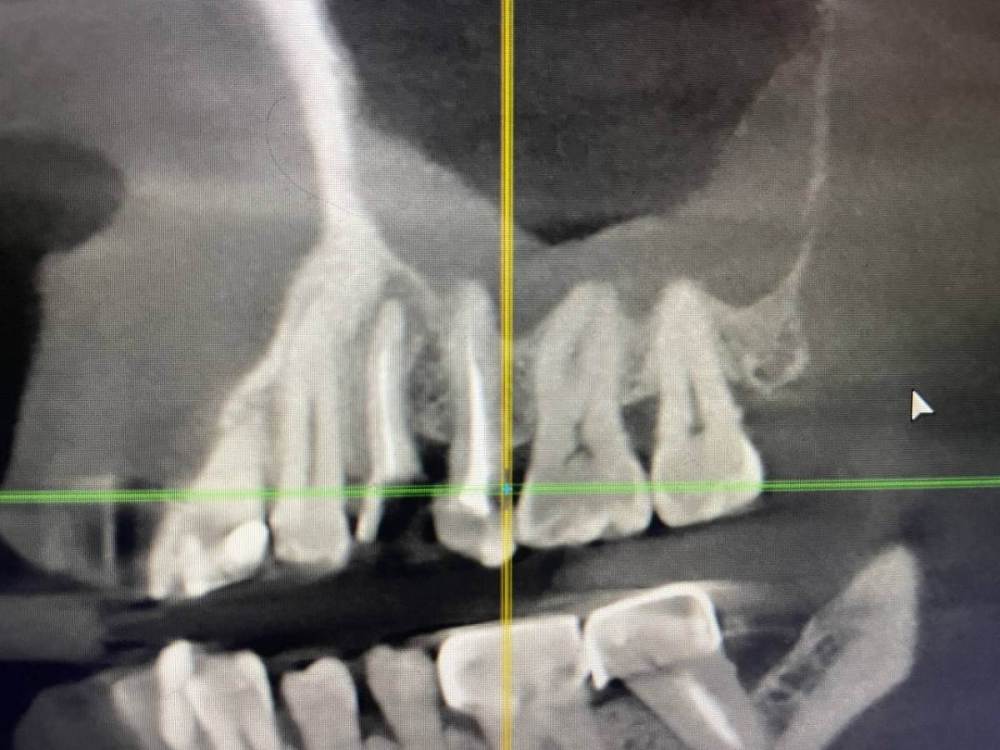

1586Doc Опубликовано 8 февраля, 2020 Поделиться Опубликовано 8 февраля, 2020 5 месяцев назад обратилась пациентка с симптоматикой периодонтита. Оценили, попробовали. Пломбировка вертикалка. 5 месяцев и контроль, боли нет, подвижности тоже. 2 Ссылка на комментарий

1586Doc Опубликовано 10 февраля, 2020 Автор Поделиться Опубликовано 10 февраля, 2020 (изменено) А где контроль на сегодня? При таком качестве снимков оценить будет тяжело.первые 2 фото снимки 9 месяц назад, до ревизии Изменено 10 февраля, 2020 пользователем 1586Doc Ссылка на комментарий

1586Doc Опубликовано 10 февраля, 2020 Автор Поделиться Опубликовано 10 февраля, 2020 (изменено) Имхо пока не вижу успеха. ((ну если еще с 46 я могу понять, 45 явно деструкция в разы меньше. 100% месяца через 3-4 назначу клкт Изменено 10 февраля, 2020 пользователем 1586Doc Ссылка на комментарий

1586Doc Опубликовано 17 января, 2021 Автор Поделиться Опубликовано 17 января, 2021 первые 3 фото, ретрит 14 зуб4.5 фото 45 зуб. 4 Ссылка на комментарий